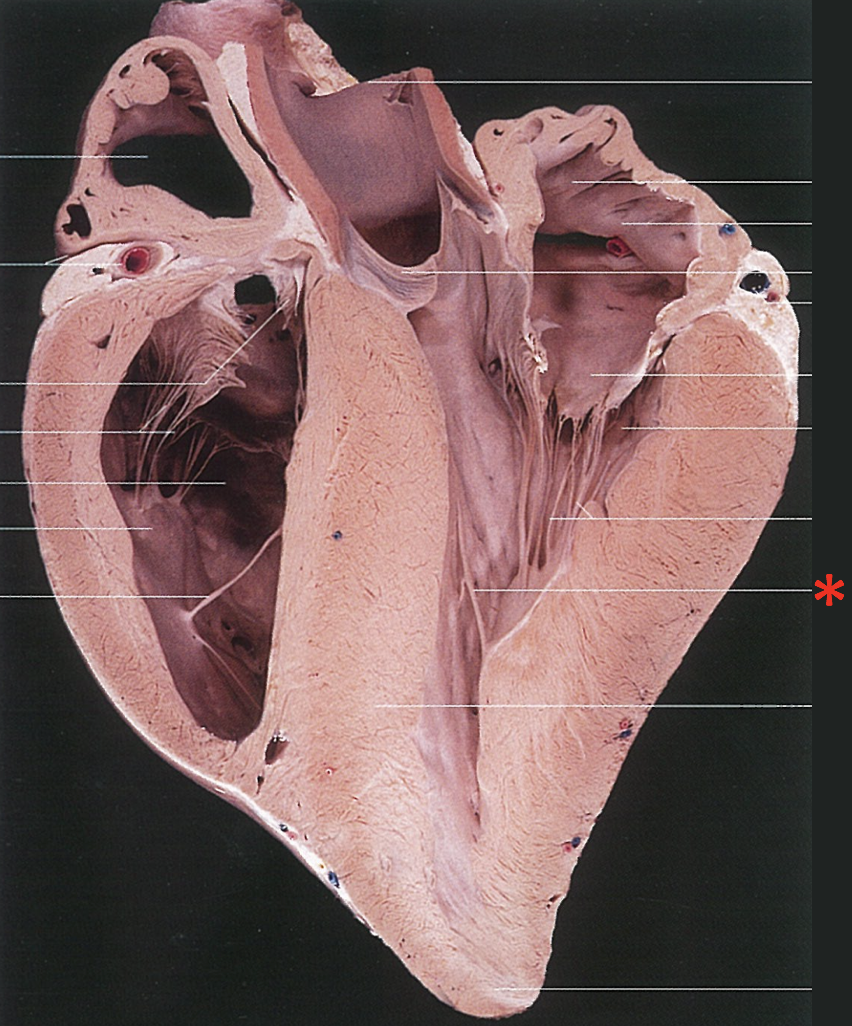

Chordae Tendinae

Left Muscular Band

Right Muscular Band

Muscular Ridges

Left Semilunar Valvula

Parietal Cup

Right Semilunar Valvula

Intermediate Semilunar Valvula

Septal Cusp

Right Ventricular Margin